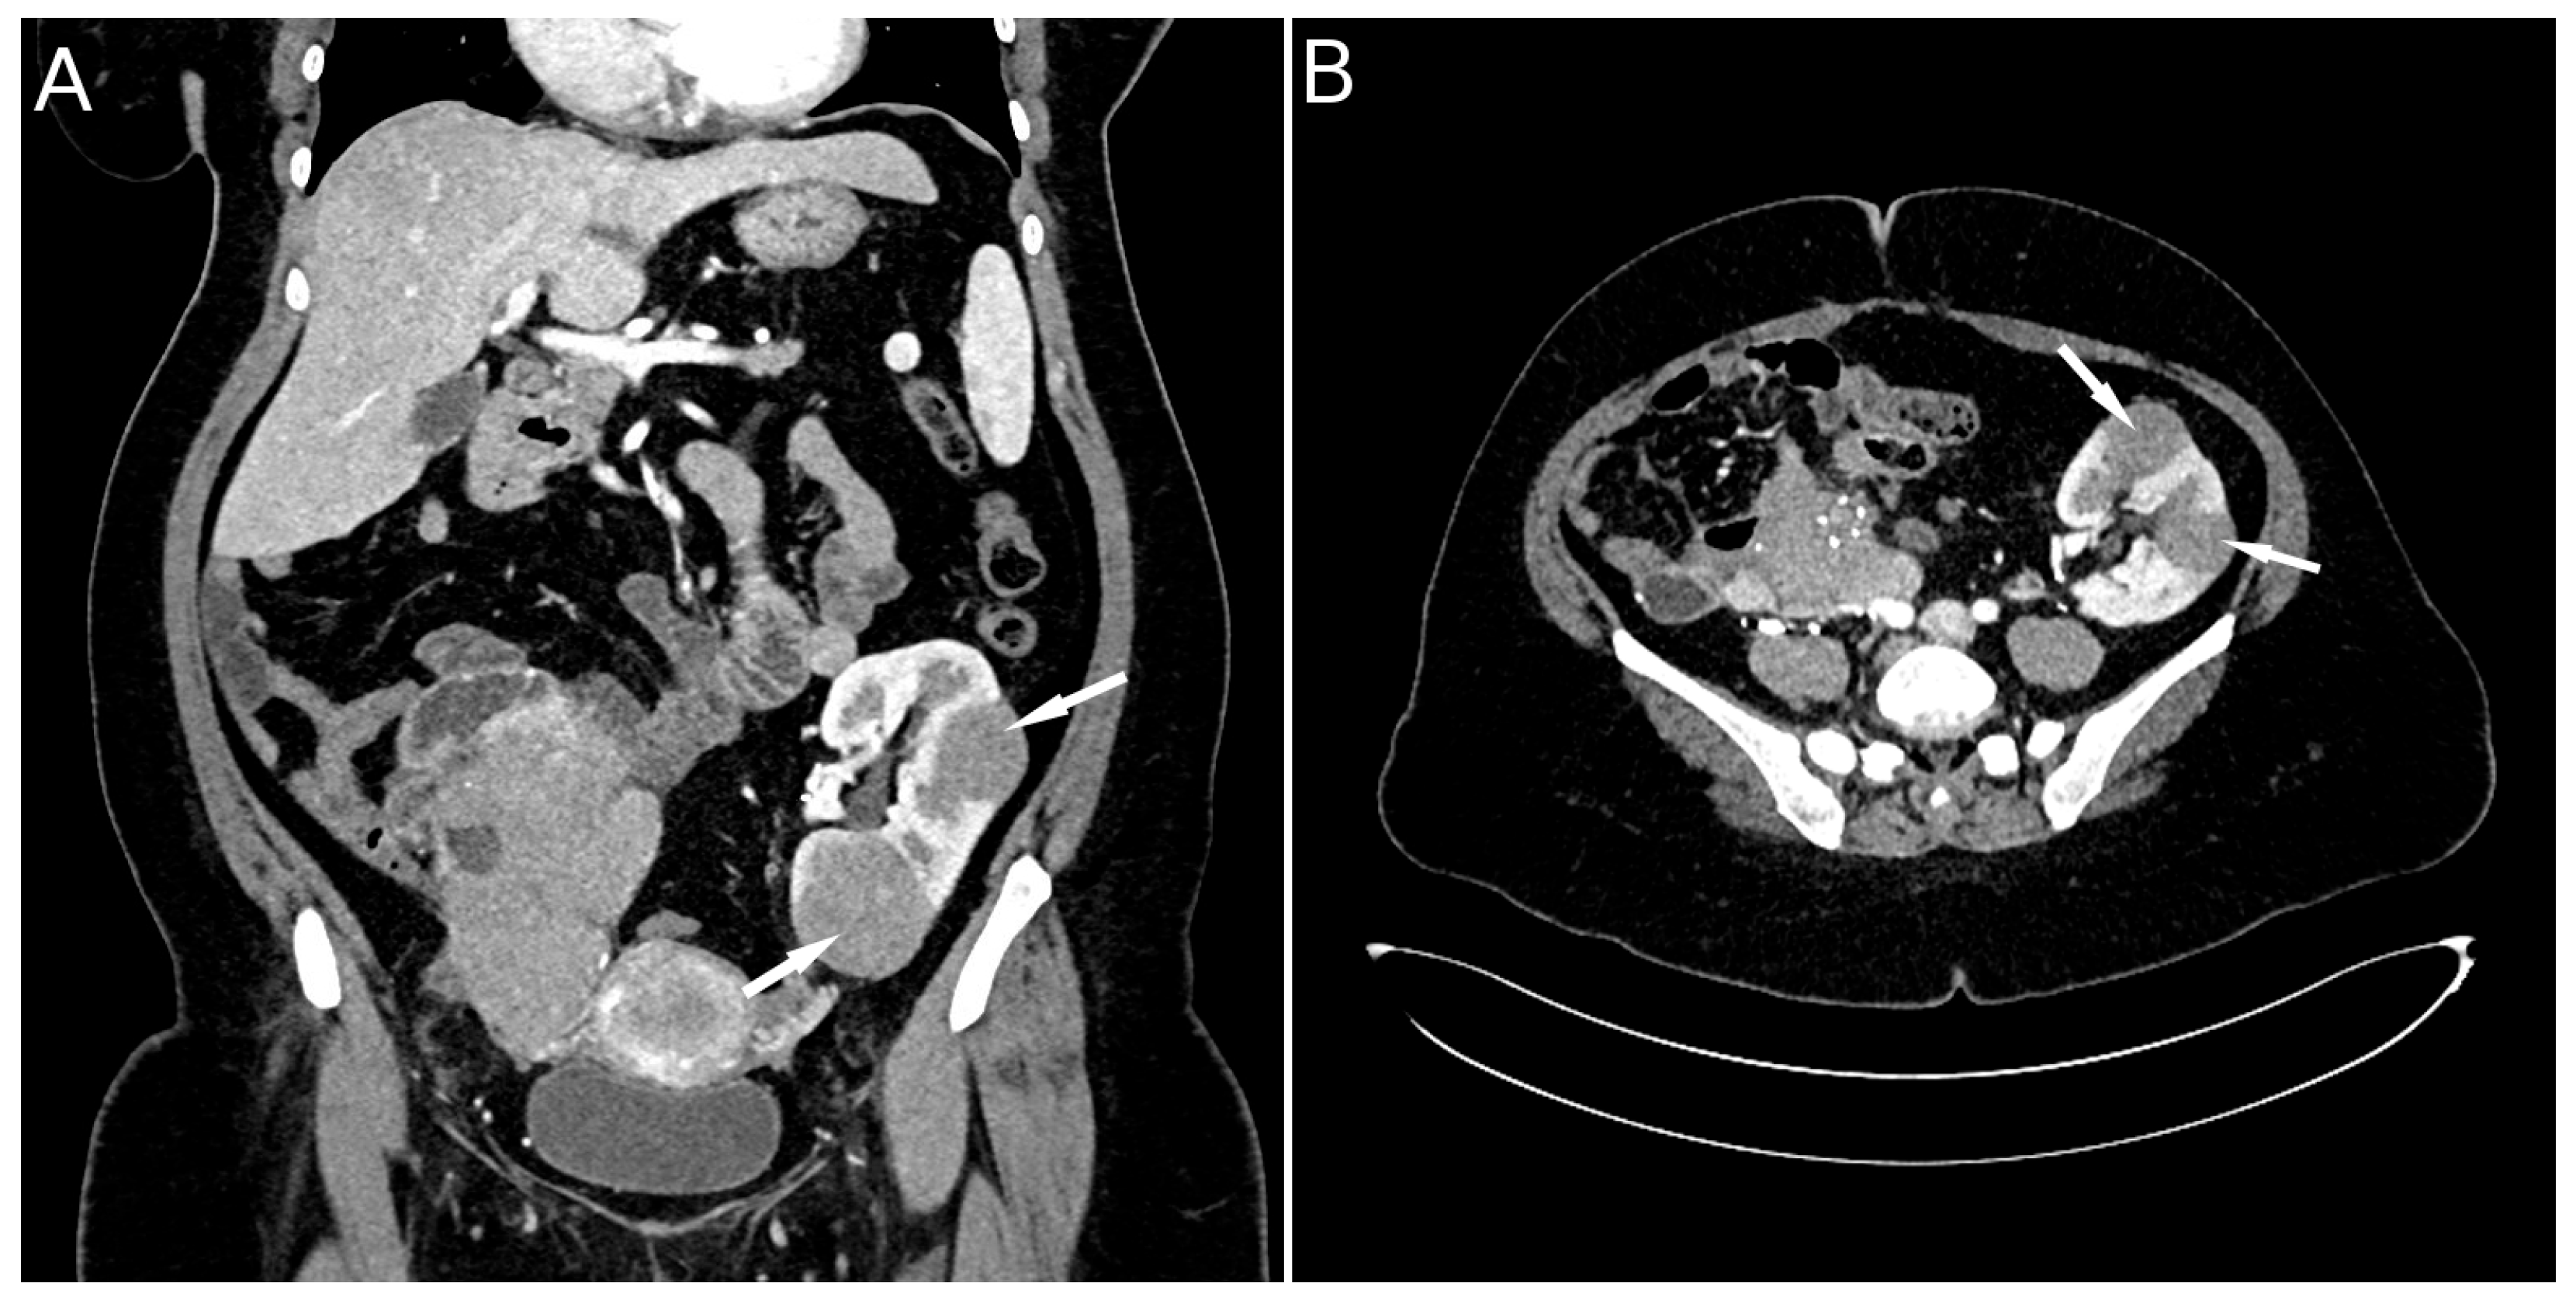

2. Case Presentation